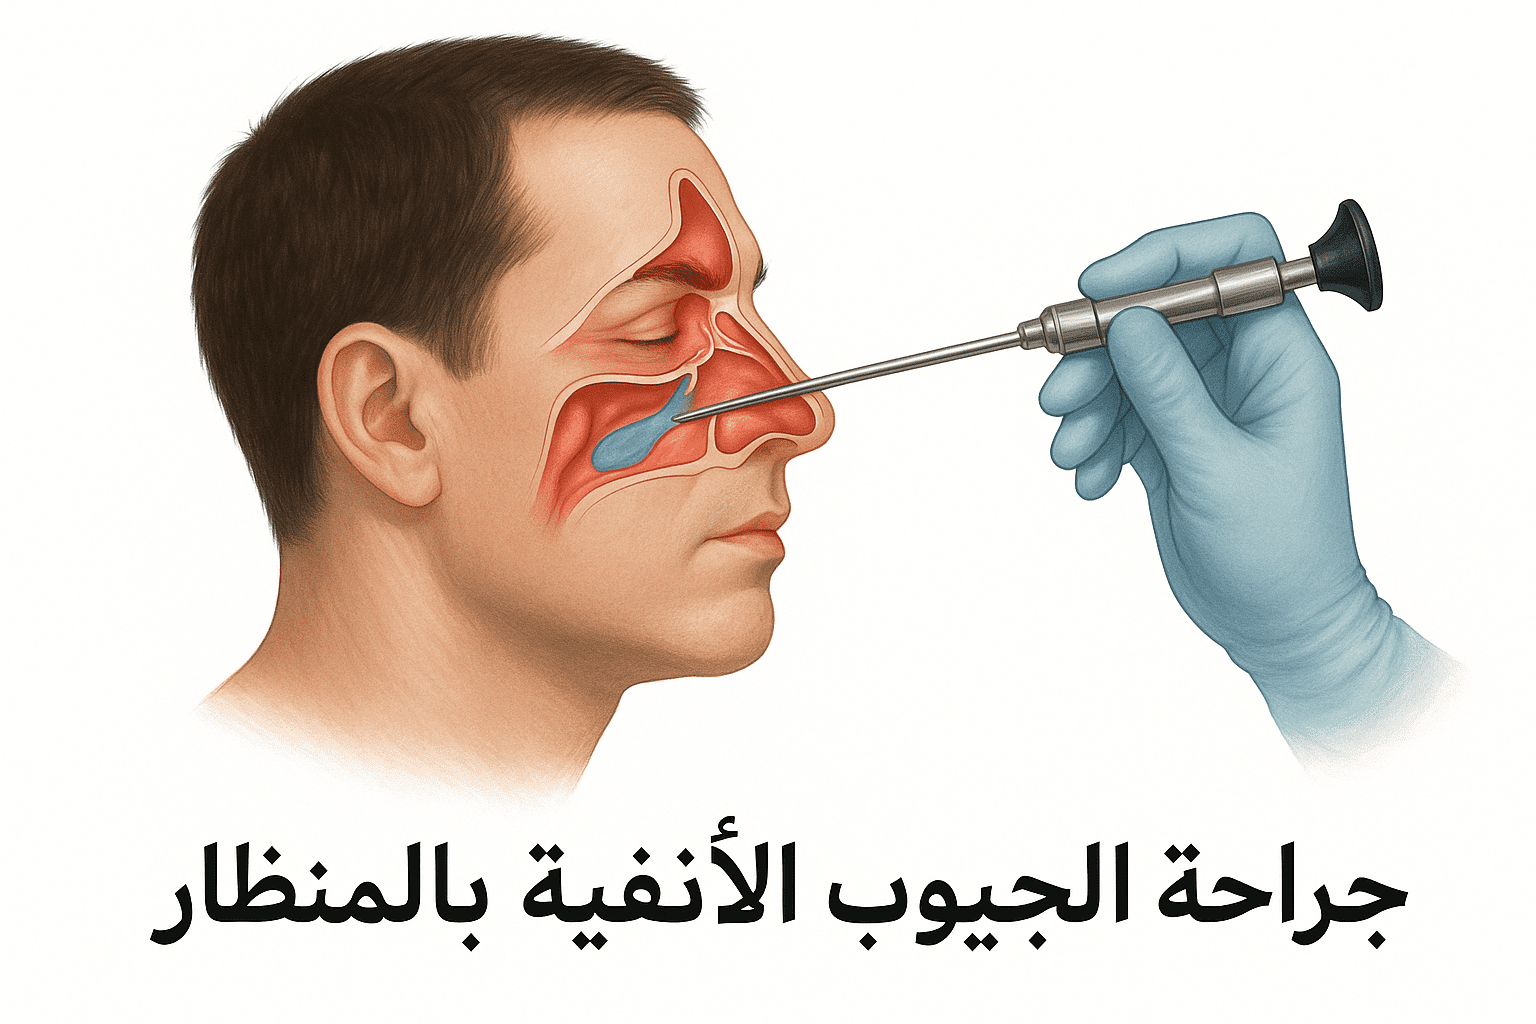

نغطي كل التخصصات الطبية

ابحث عن الجراحة او المرض الذي تبحث عن علاج له

استیعاب کافة الحالات الطبیة لشمولیة التخصصات